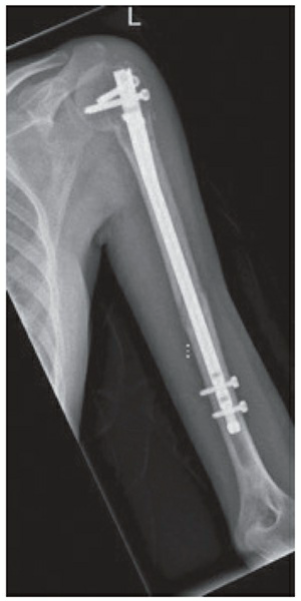

Certainly, Examiner. The X-ray image (Figure 1) reveals a displaced fracture located in the middle third of the left humerus. There are no signs of dislocation in the left shoulder or elbow joints. Clinically, the patient presented with focal pain and deformity in the left middle humerus, with no pain at the shoulder or elbow joints. Based on these findings, the fracture can be classified as a mid-shaft humerus fracture.

🔍 Click to enlargeFigure 4: Plate and screw fixation of a distal third humeral shaft fracture. - **Intramedullary Nailing (IMN):**

🔍 Click to enlargeFigure 5: Intramedullary nail fixation of a humeral shaft fracture. - **External Fixation:**